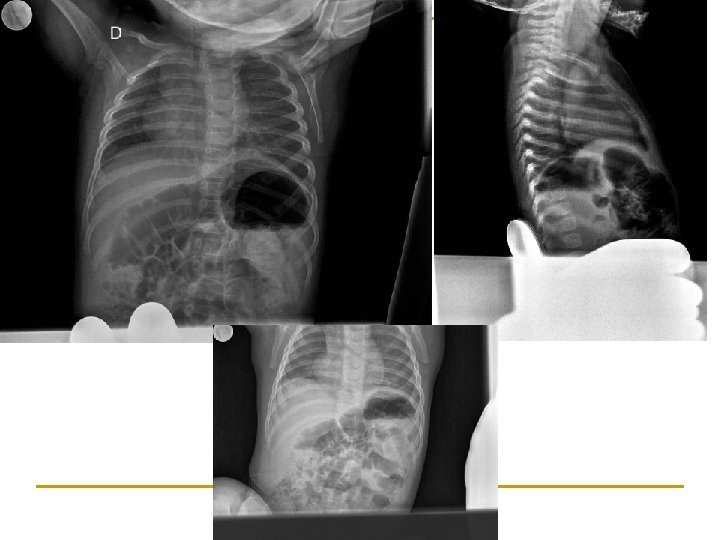

Ventral Caudal Dorsal Ventral Cefalico